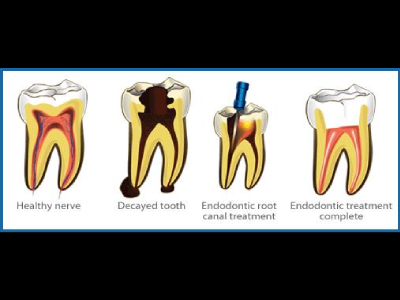

He has further enhanced his expertise by attending various advanced courses in Endodontics,

Prosthodontics, Oral Surgery, and Implantology.

experienced dentist, he specializes in procedures such as Root Canal Treatment, Dental

Extractions, Dental Implants, Crowns, Full Mouth Rehabilitation, and Clear Aligners

We provide a wide range of dental services which includes Oral Prophylaxis, Tooth Extraction, Tooth Fillings, Veneers, Complete and partial dentures, Crowns, Fixed Bridges, Braces, Retainers, Periodontal/Gum Treatment, Root Canal Treatment, Bleaching/Teeth Whitening, Cosmetic Dentistry, Minor Oral Surgical procedures, and Paediatric Dentistry.